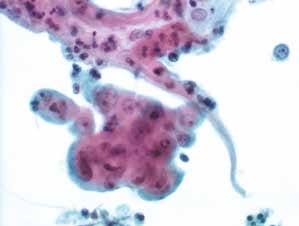

图4-68 非角化型鳞癌(高倍、液基、巴氏染色)

癌细胞成团排列,细胞核异型性明显,染色质粗颗粒状,胞质蓝染,高核质比,肿瘤素质可见。